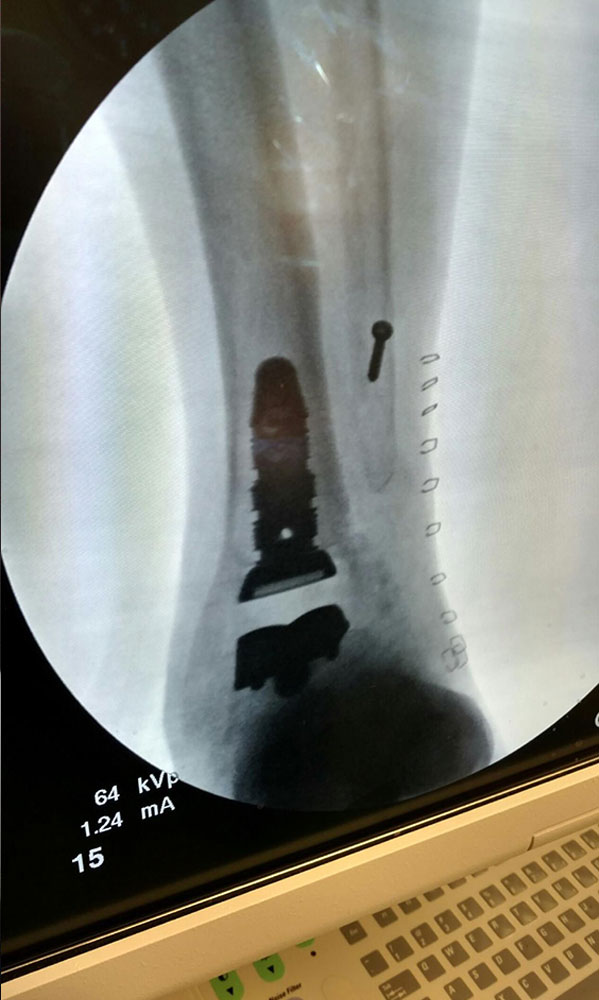

Ten years of severe ankle pain with a mal-positioned ankle fusion is now relieved! Patient is now walking with pain-free ankle motion!